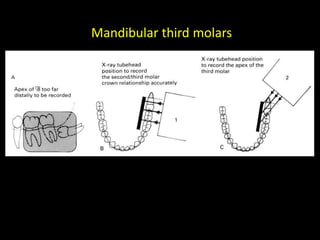

3. Special considerations for intra-oral radiography include techniques for mandibular third molars, gagging patients, endodontic procedures, edentulous ridges, and pediatric patients.